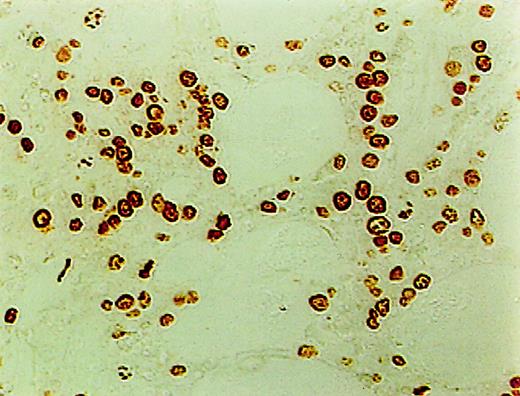

ISEL of fragmented DNA was performed on plastic embedded BM biopsies. A distinct brown staining in the nucleus identified a cell as being engaged in DNA cleavage. Among the 10 cases studied, 2 cases showed high positivity; 2, intermediate; 4, low; and 1, no ISEL positivity. When comparing MDS patients to the healthy donors, an increase in apoptosis was noted in MDS patients (3+ in MDS patients vs 0+ in donors; P = .1). All 3 lineages of hematopoietic cells, including the myeloid, erythroid, and megakaryocytic cells, were found to be undergoing apoptosis. Furthermore, in almost every case, stromal cells were also found to be apoptotic (Figure1).

High incidence of apoptosis involving hematopoietic and stromal cells in the BM of MDS patients using ISEL.

Brown staining is noted (original magnification × 400).